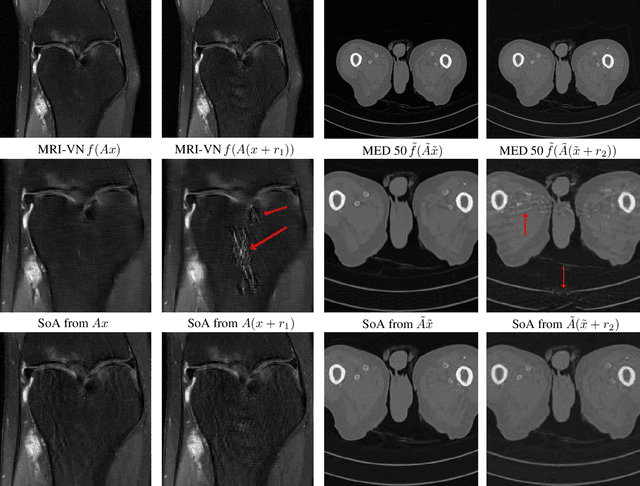

Abstract:Deep learning, due to its unprecedented success in tasks such as image classification, has emerged as a new tool in image reconstruction with potential to change the field. In this paper we demonstrate a crucial phenomenon: deep learning typically yields unstablemethods for image reconstruction. The instabilities usually occur in several forms: (1) tiny, almost undetectable perturbations, both in the image and sampling domain, may result in severe artefacts in the reconstruction, (2) a small structural change, for example a tumour, may not be captured in the reconstructed image and (3) (a counterintuitive type of instability) more samples may yield poorer performance. Our new stability test with algorithms and easy to use software detects the instability phenomena. The test is aimed at researchers to test their networks for instabilities and for government agencies, such as the Food and Drug Administration (FDA), to secure safe use of deep learning methods.